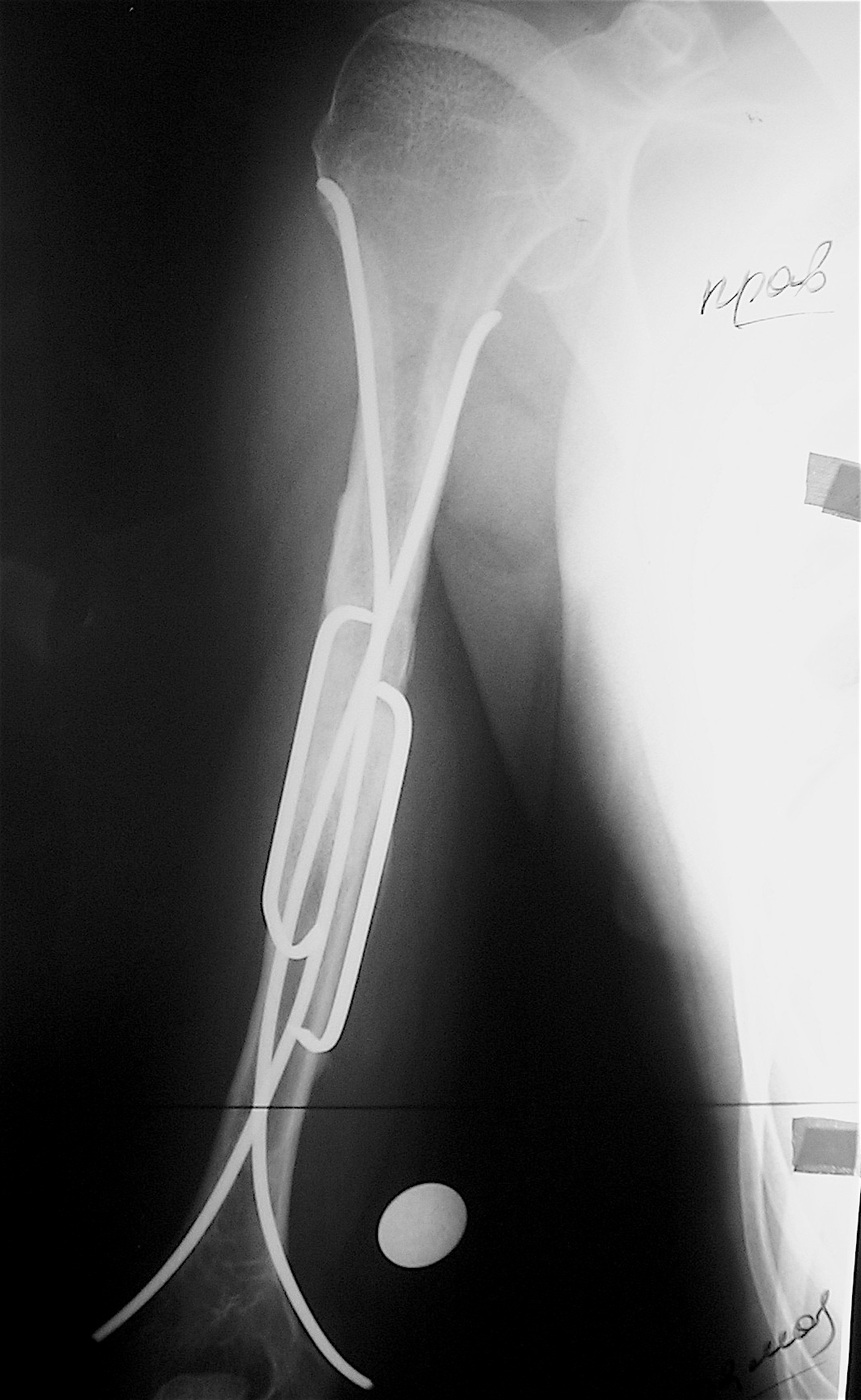

Закрытый, патологический перелом в с/з правой плечевой кости на фоне аневризмальной кисты диафиза правой плечевой кости.

Выполнена операция: экскохлеация кисты, остеосинтез титановыми эластичными стержнями и металлической скобой, аллопластика патологического очага материалом «Лиопласт».